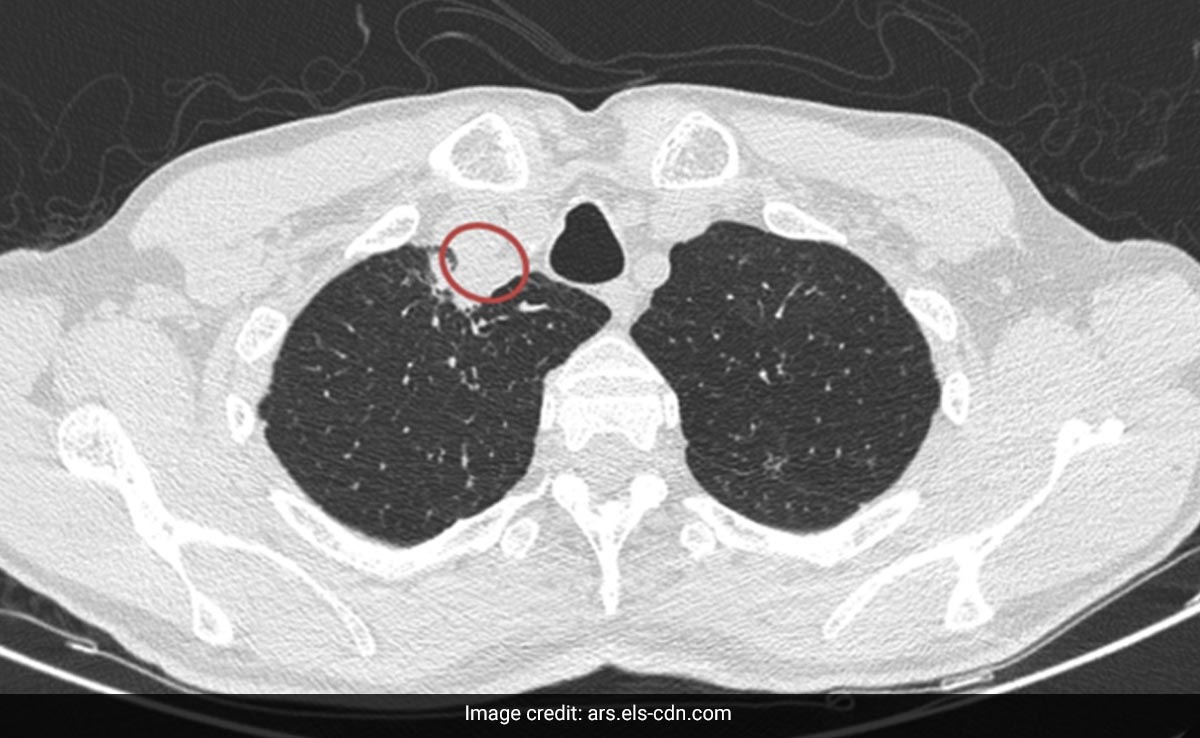

डॉक्टरों के अनुसार, पीड़ित व्यक्ति की गर्दन में फोड़े का पता चला. उसे निकालने के लिए ऑपरेशन किया गया. इसके बाद एक्स-रे में कुछ भी असामान्य नहीं निकला और फिर रोगी को एंटीफंगल दवा का कोर्स दिया गया.